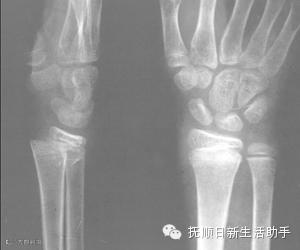

骨折

确定有骨折后,一定要对伤肢(指)作固定再送医院,否则骨折断端异常活动,会加重损伤。可因地制宜用木板、木棍、树枝、竹竿、杂志等作为固定用的临时夹板。若无上述材料,可将上肢固定在躯干上,下肢固定在对侧的健肢上。